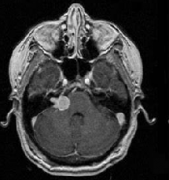

听神经瘤是脑内桥小脑角区(CPA)比较常见的脑肿瘤,中老年人多见。听神经瘤发生于前庭神经雪旺氏细胞鞘,因为面神经、听神经、前庭上和前庭下神经组...

当耳鸣患者去耳鼻喉科寻求帮助时,诊断的一步通常是听力学检查和核磁共振成像(MRI)。磁共振检查是为了排除听觉神经瘤或其他器质性耳鸣的可能性...